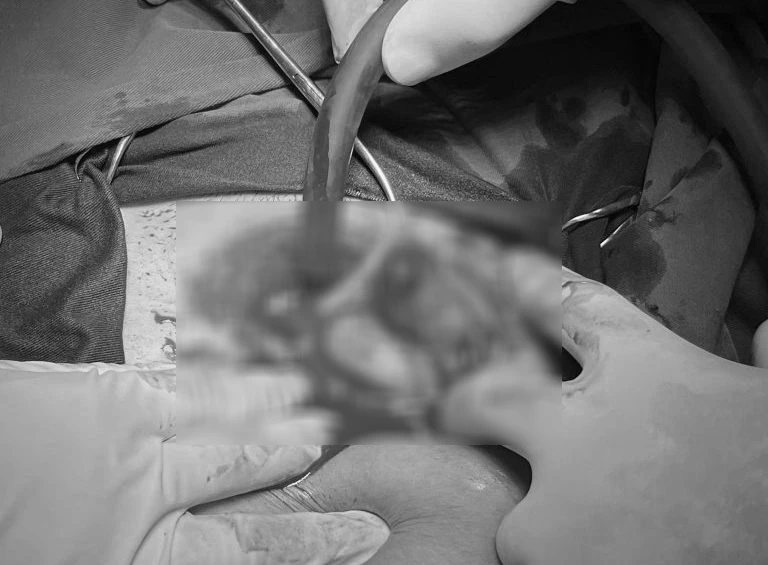

Bác sĩ phẫu thuật loại bỏ khối chửa ngoài tử cung cho thai phụ mang song thai. Ảnh BVCC

BS CKI Đinh Thị Sỹ, Phó trưởng khoa Phụ sản, TTYT Yên Lập, cho biết đây là trường hợp mang song thai hiếm gặp. Nếu không can thiệp kịp thời, thai ngoài tử cung có thể vỡ, chảy máu ồ ạt, đe dọa sức khỏe mẹ và thai còn lại.

Sau khi thăm khám cận lâm sàng, thai phụ và gia đình được các bác sĩ tư vấn, giải thích rõ về tình trạng, thống nhất phẫu thuật loại bỏ khối chửa ngoài tử cung.